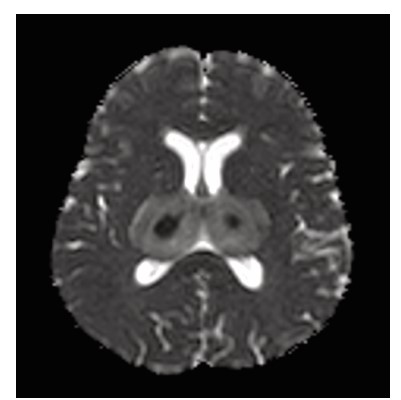

Dengue fever, a mosquito borne viral illness, is endemic in many parts of the world, particularly in tropical and subtropical regions. It is caused by four distinct serotypes (DENV 1–4) of single stranded RNA viruses from the Flaviviridae family. Although it is generally considered non-neurotropic, certain strains, especially DENV-2 and DENV-3, have been associated with neurological involvement. Neurological complications can include encephalopathy, encephalitis, meningitis, acute disseminated encephalomyelitis (ADEM), stroke, and Guillain-Barré syndrome. Dengue encephalitis, a relatively uncommon but serious manifestation, arises from direct viral invasion of neural tissue. This case report presents a patient with altered mental status and characteristic MRI findings symmetrical involvement of the thalami and cerebellum, known as the “double doughnut sign” indicative of dengue encephalitis. Cerebrospinal fluid analysis confirmed the diagnosis. Early recognition, neuroimaging, and supportive management with immunomodulation played a crucial role in the patient’s recovery. Clinicians should maintain a high index of suspicion for dengue encephalitis in endemic areas when encountering unexplained encephalopathy.